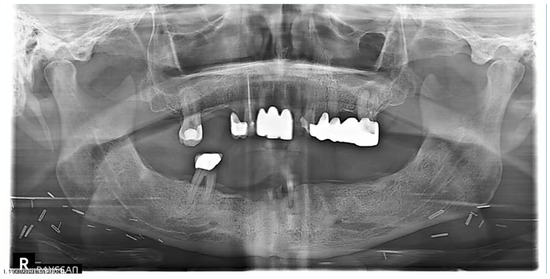

| 1 | M | 69 | Squamous cell carcinoma | Base of Tongue (Oropharynx) | 70 Gy/(Yes) | Mandibular First Molar (#19) | High | Complete Healing |

| 2 | M | 70 | Squamous cell carcinoma | Ventral Tongue/Floor of Mouth (Oral Cavity) [Right] | 70 Gy/(Yes) | Mandibular Incisors and First Molar (#24, #25, #26, and #30) | High | Complete Healing |

| 3 | F | 59 | Squamous cell carcinoma | Tonsil (Oropharynx) [Right] | 70 Gy/(Yes) | Mandibular First Molar (#19) | Moderate | Complete Healing |

| 4 | M | 75 | Adenoid cystic carcinoma | Hard palate/Maxillary Sinus (Oral Cavity) [Left] | 66 Gy/(No) | Mandibular Second Molars (#18 and #31) | Moderate | Complete Healing |